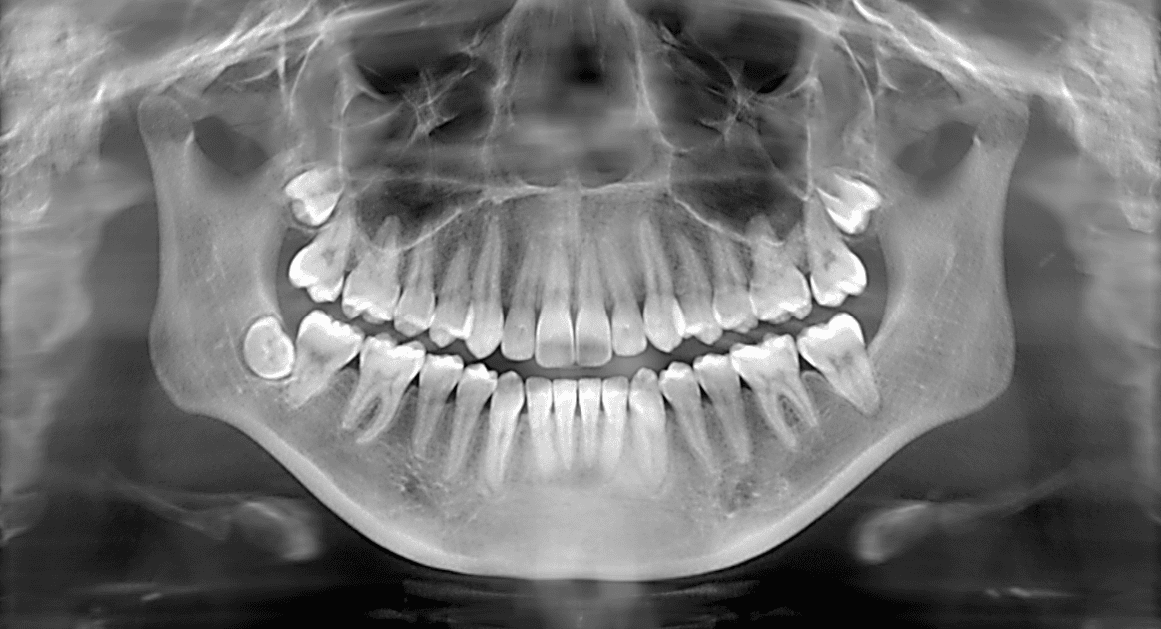

Facts About Dental X-Rays

Dental x-rays are clear picture of the teeth, bones, gums and soft tissues around them. These are helpful in finding problems with teeth, mouth and jaw. Dental x-rays are integral